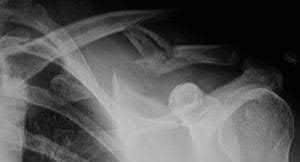

A 44-year-old male is struck by a vehicle while riding his bike. In the trauma bay, he complains of right shoulder pain . Upper extremity physical exam reveals no neurologic deficits, and an initial radiograph of the shoulder is shown in Figure A. A CT scan of the shoulder shows 1cm of posterior displacement of the tuberosity fragment. Which of the following is true regarding this injury?

The radiograph in Figure A demonstrates a posteriorly displaced greater tuberosity fracture. These injuries are often associated with anterior shoulder dislocations, and concomitant rotator cuff tears. The subscapularis attaches to the lesser tuberosity, and is not a deforming force. Open reduction and internal fixation (ORIF) is usually the treatment of choice, and it is well accepted that more than 5mm of displacement is an indication for surgery in patients that require overhead function of the arm.

Flatow et al evaluated 12 patients who were an average of five years status post ORIF of displaced greater tuberosity fractures. All fractures healed without postoperative displacement. Six patients had an excellent result and six had a good result.

Platzer et al retrospectively analyzed functional and radiographic results of 52 patients with operative treatment of displaced greater tuberosity fractures at an average time of 5.5 years from surgery compared to 9 patients with equivalent injuries treated non-operatively. Evaluation of the results of the surgical study group and the nonoperative control group, patients with reduction and fixat ion of greater tuberosity fractures had significantly better

results on shoulder function than did those with conservative treatment.